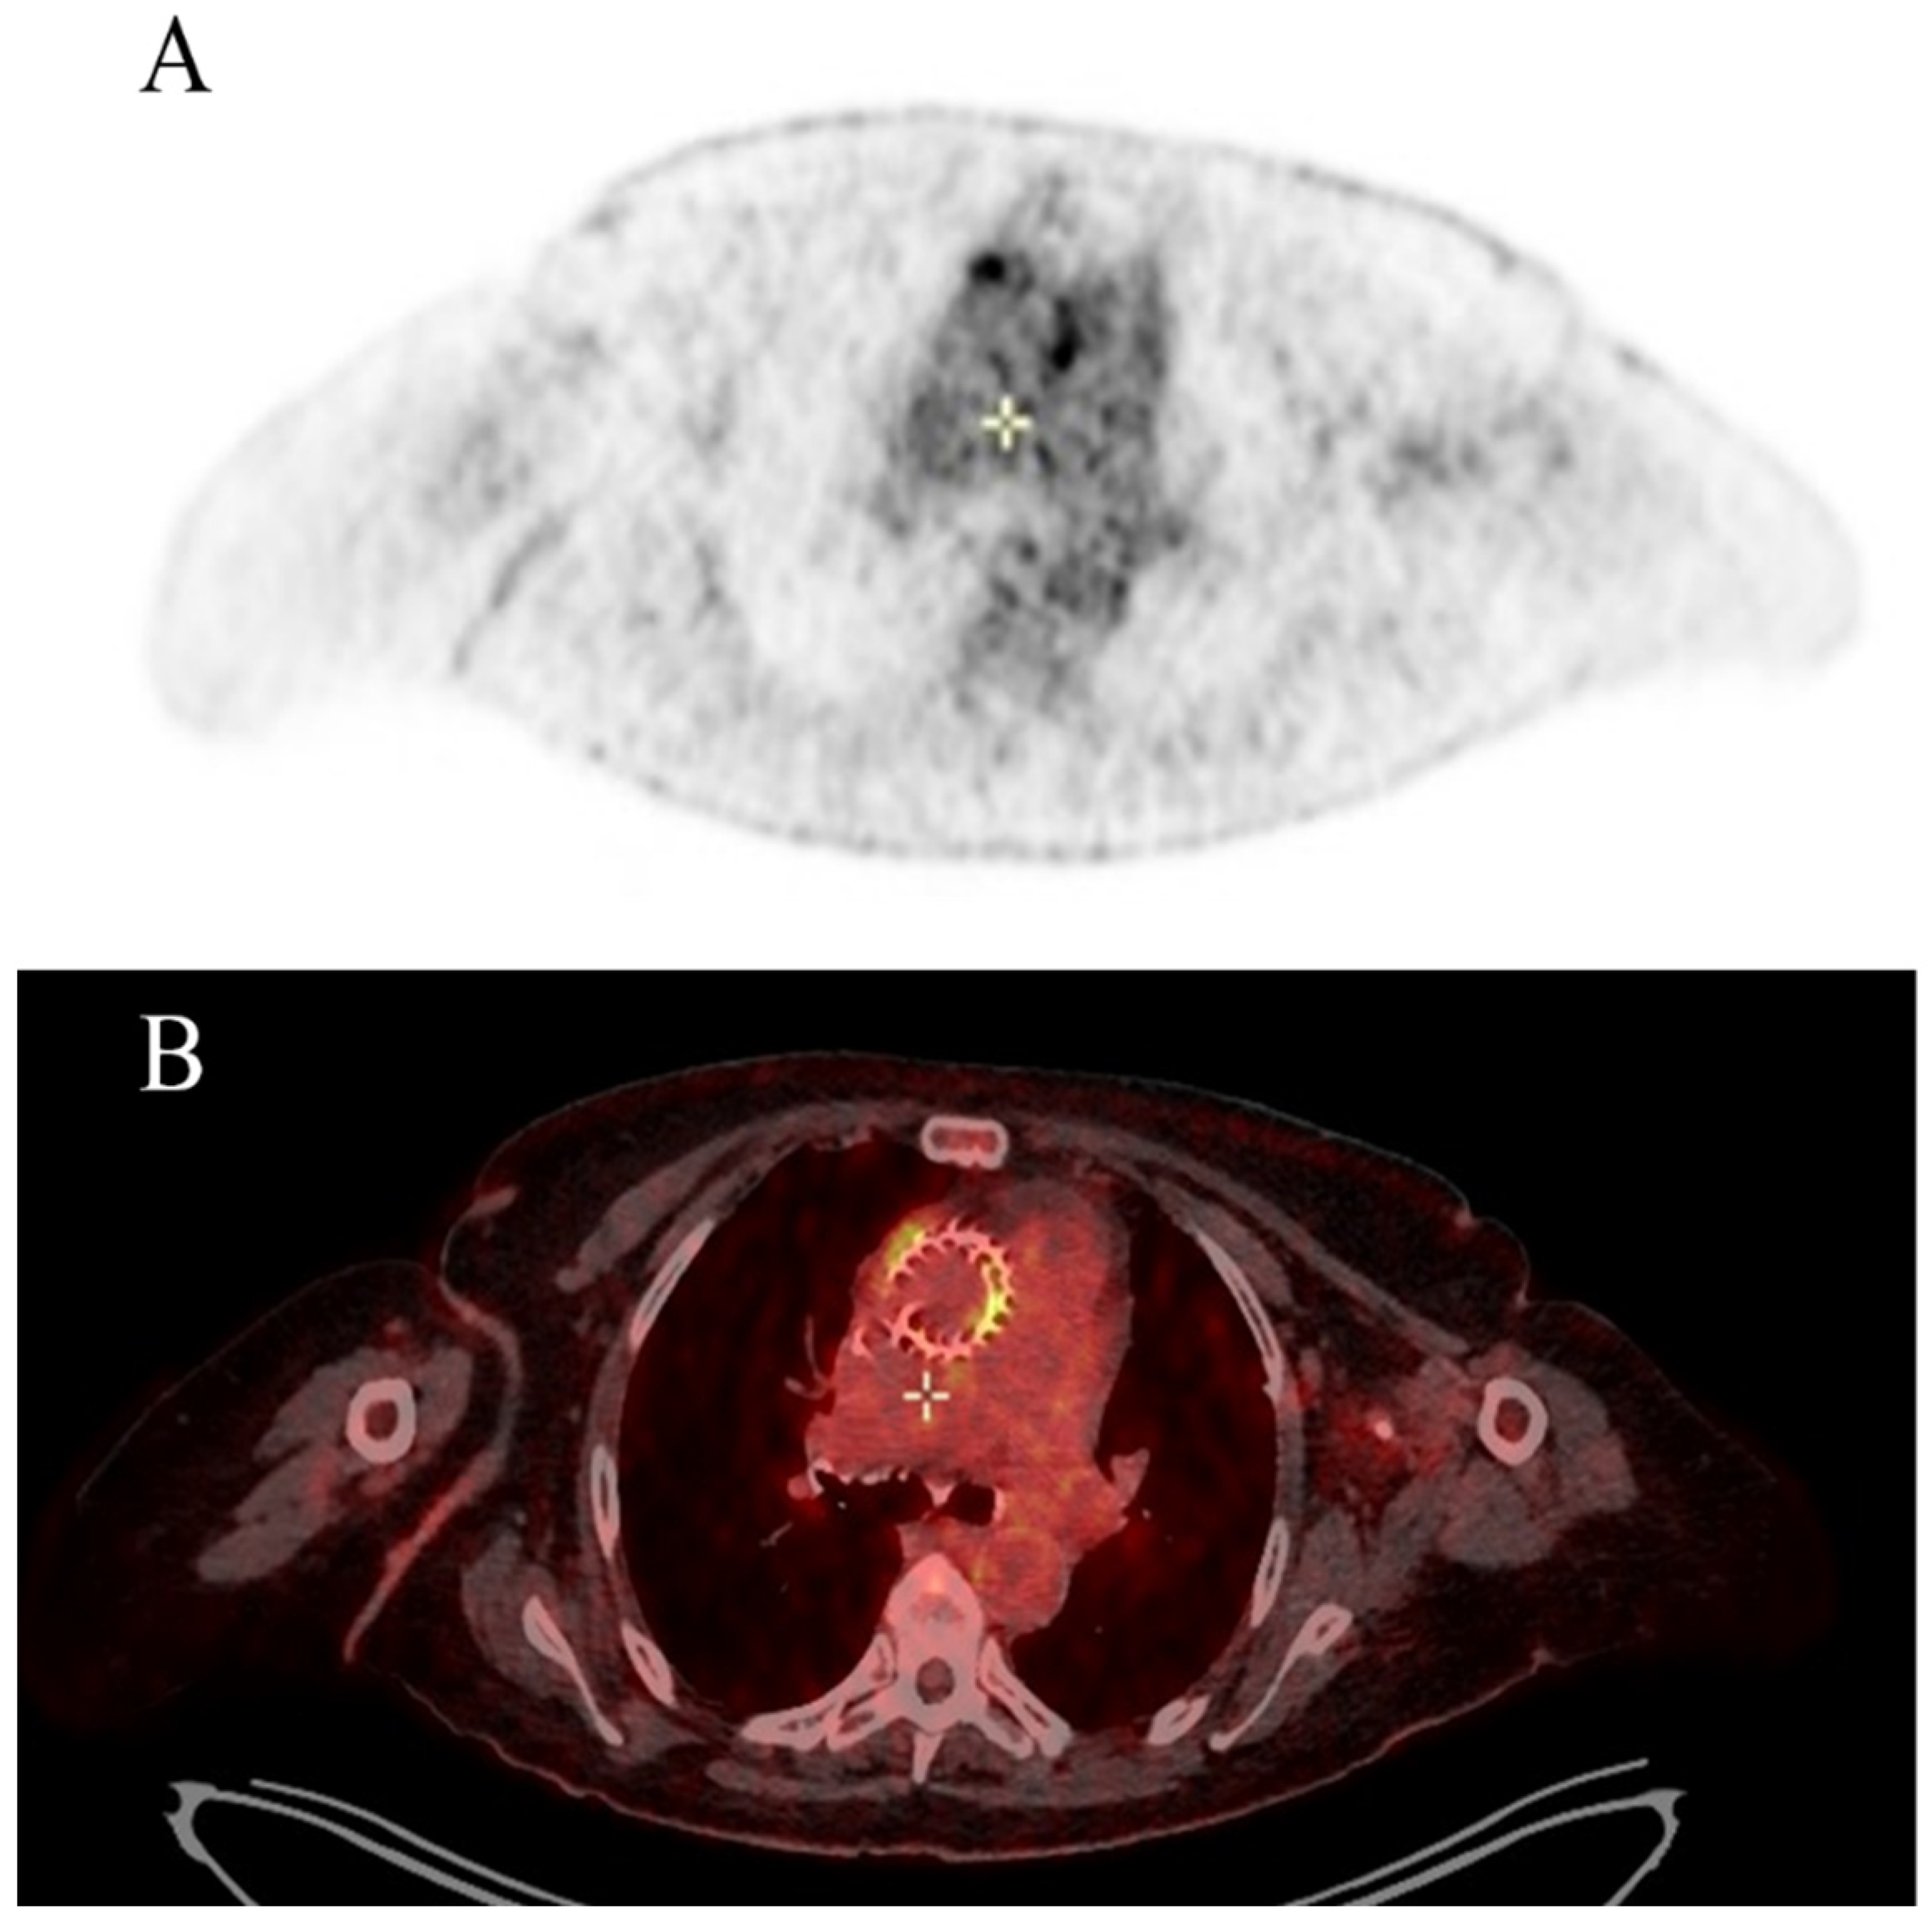

- Wang, T.K.M.; Sánchez-Nadales, A.; Igbinomwanhia, E.; Cremer, P.; Griffin, B.; Xu, B. Diagnosis of infective endocarditis by subtype using (18)F-fluorodeoxyglucose positron emission tomography/computed tomography: A contemporary meta- analysis. Circ. Cardiovasc. Imaging 2020, 13, e010600. [Google Scholar] [CrossRef] [PubMed]